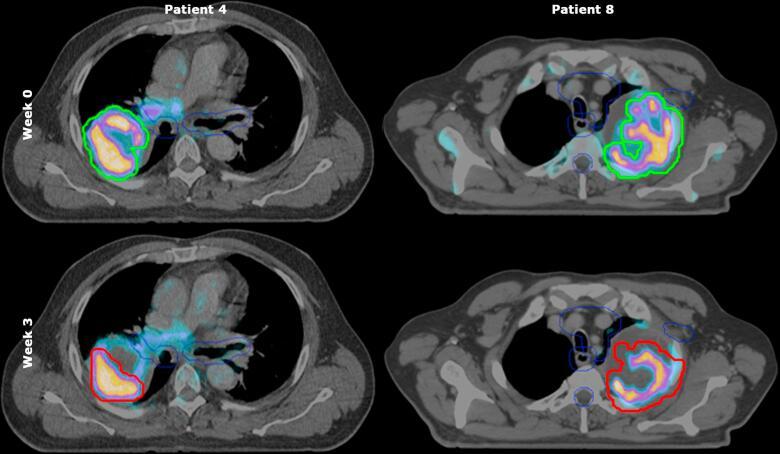

Prognosis of locally advanced non-small cell lung cancer remains poor despite chemoradiation. This planning study evaluated a stereotactic boost after concurrent chemoradiotherapy (30 × 2 Gy) to improve local control. The maximum achievable boost directed to radioresistant primary tumor subvolumes based on pre-treatment fluorine-18 fluorodeoxyglucose positron emission tomography/computed tomography (F-FDG-PET/CT) (pre-treatment-PET) and on early response monitoring F-FDG-PET/CT (ERM-PET) was compared.

MATERIALS AND METHODS

For ten patients, a stereotactic boost (VMAT) was planned on ERM-PET (PTV) and on pre-treatment-PET (PTV), using a 70% SUV threshold with 7 mm margin to segmentate radioresistant subvolumes. Dose was escalated till organ at risk (OAR) constraints were met, aiming to plan at least 18 Gy in 3 fractions (EQD 84 Gy/BED 100.8 Gy).

In five patients, PTV was 9-40% smaller relative to PTV. Overlap of PTV with OARs decreased also compared to overlap of PTV with OARs. However, any overlap with OAR remained in 4/5 patients resulting in minimal differences between planned dose before and during treatment. Median dose (EQD) covering 99% and 95% of PTV were 15 Gy and 18 Gy respectively. Median boost volume receiving a physical dose of  ≥ 18 Gy (V18) was 88%. V18 was ≥ 80% for PTV in six patients.

A significant stereotactic boost to volumes with high initial or persistent F-FDG-uptake could be planned above 60 Gy chemoradiation. Differences between planned dose before and during treatment were minimal. However, as an ERM-PET also monitors changes in tumor position, we recommend to plan the boost on the ERM-PET.